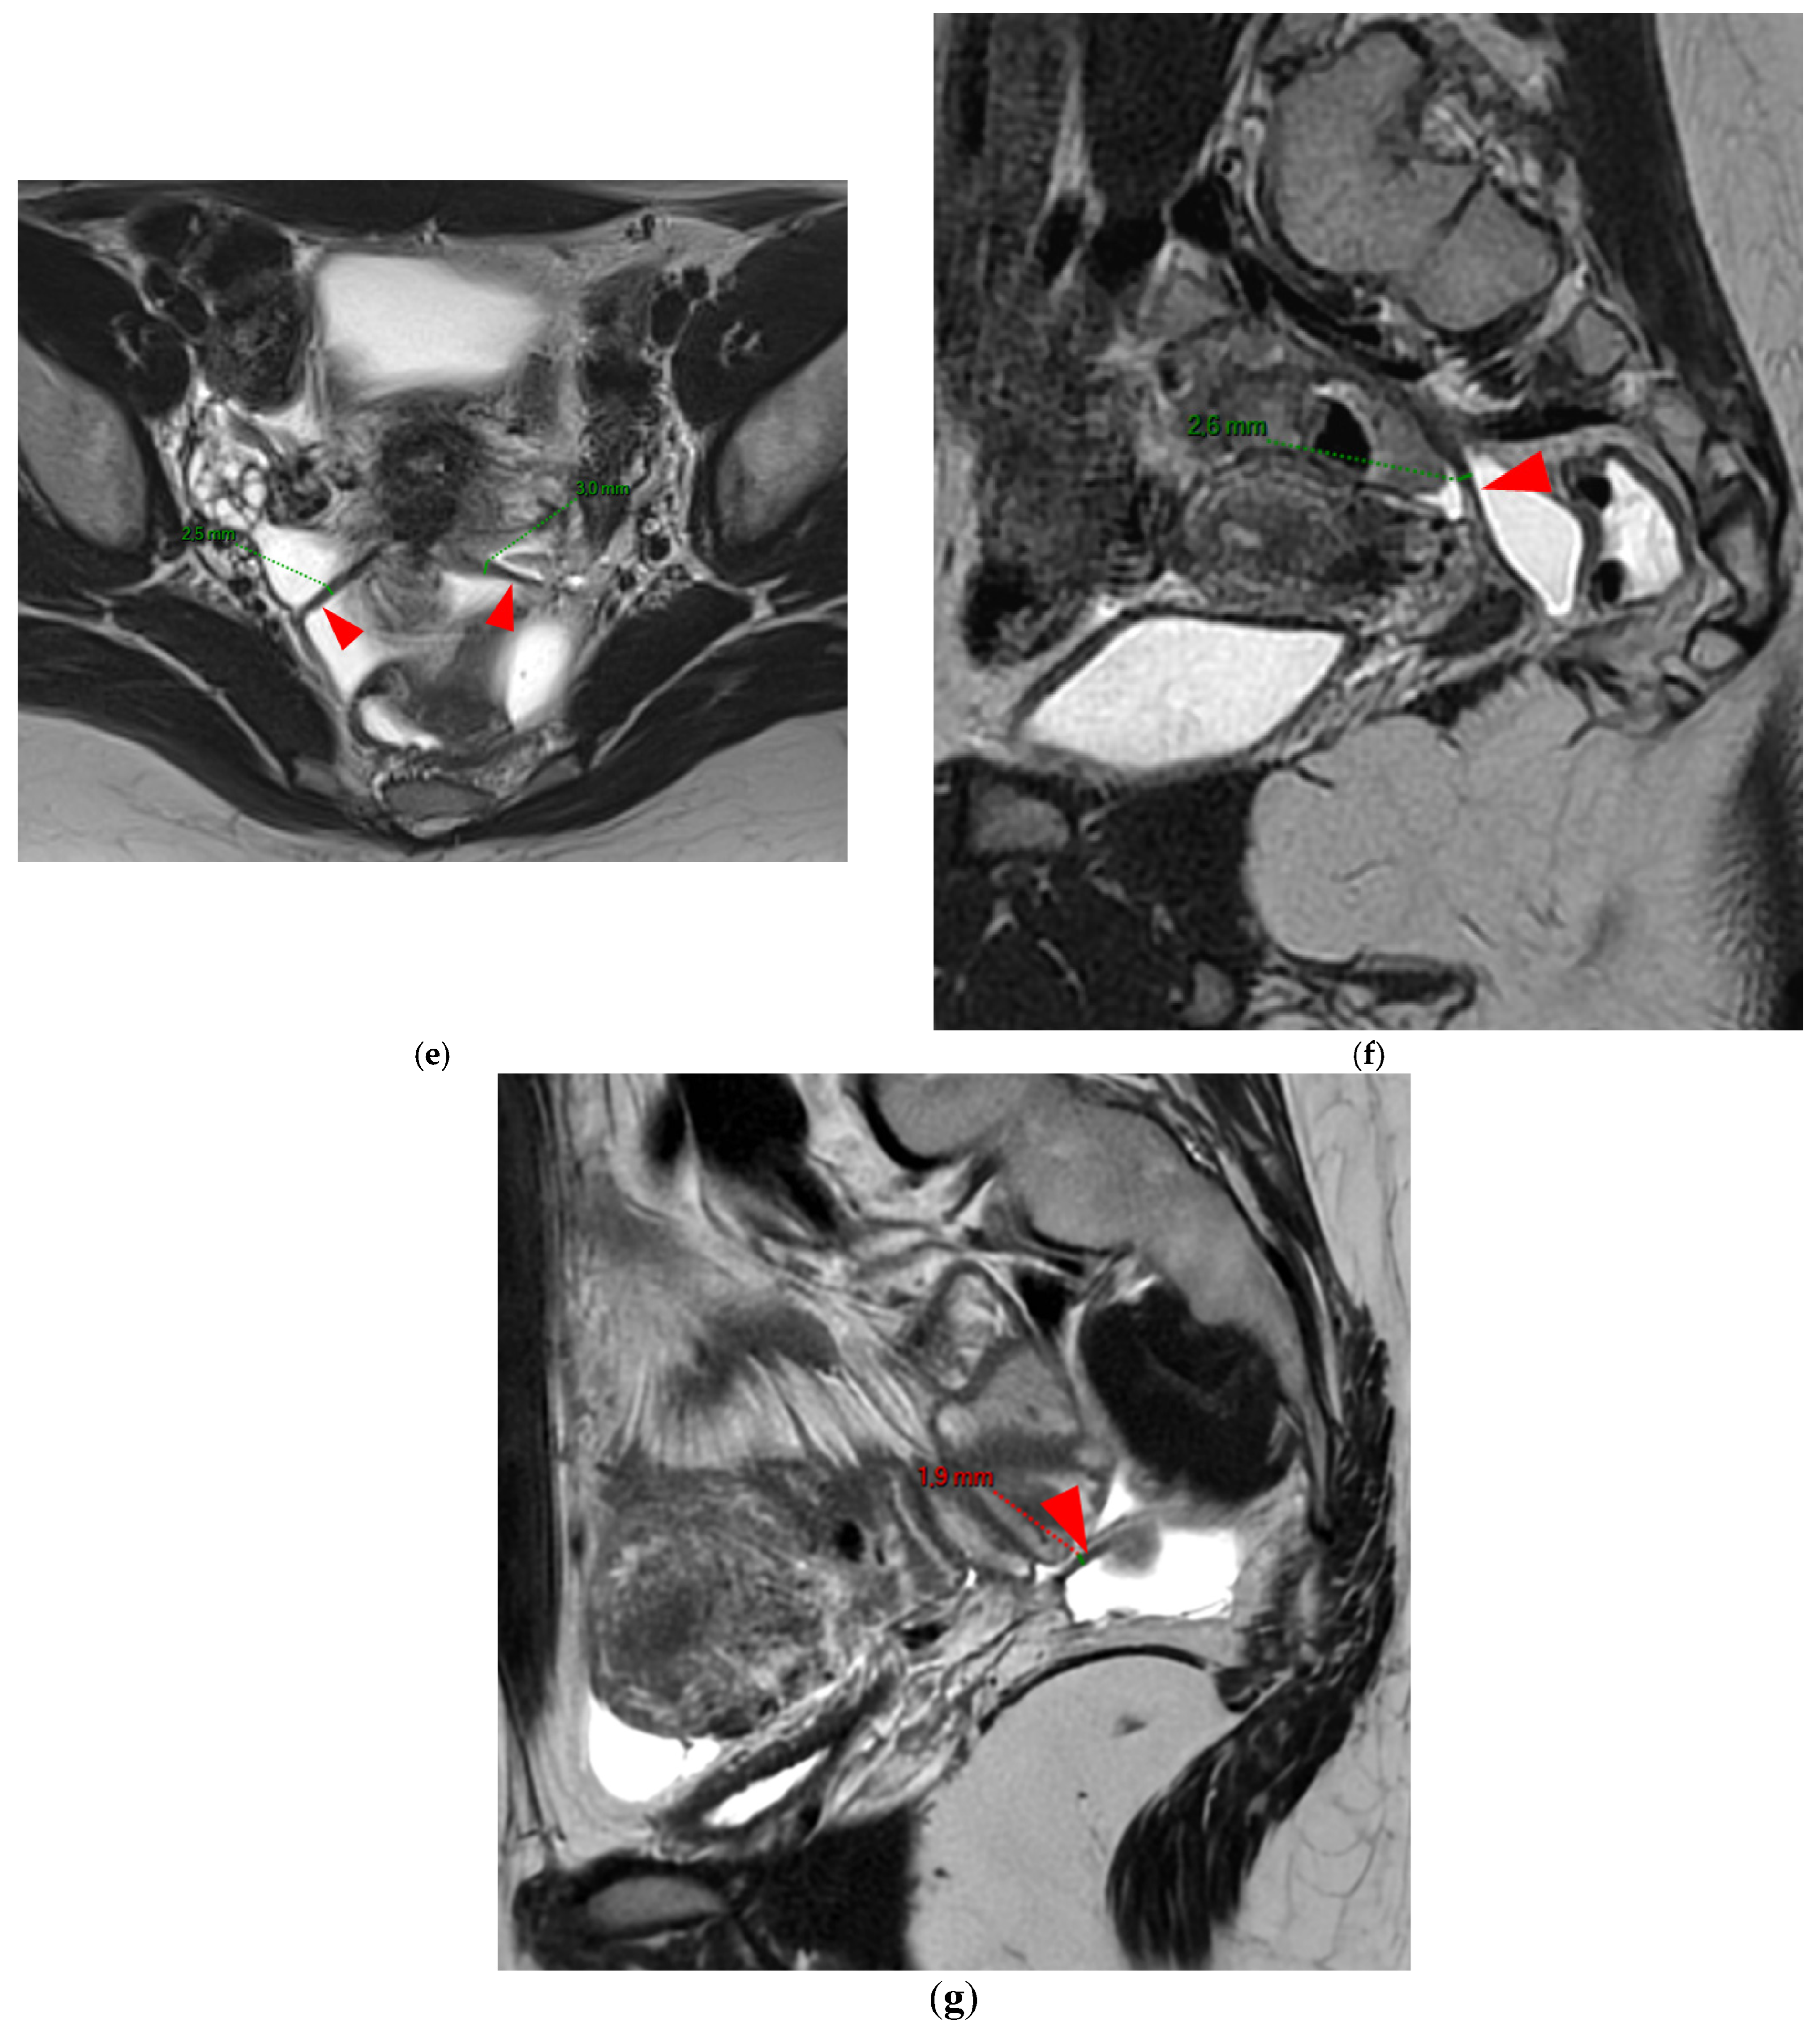

A type 3B USL (Figure 4), in addition to being thickened, has a notched surface with slightly irregular margins, or a caliber disparity with focal thickening, or appears “stiffened”, which means it loses its curvilinearity to exhibit a steep vertical orientation in the sagittal plane or a “bowstringing” of the USL in the sagittal or axial planes. Occasionally, a USL might appear thin but “stiffened”, which would upgrade it from a type 2 to a type 3B.

Figure 4. Pelvic MRI scans of seven patients with HTD type 3B USLs. (a) Sagittal T2WI: a thickened (2.1 mm) and stiffened right USL (arrowhead) with “bowstringing”. (b) Axial T2WI: a caliber disparity (dashed arrows) with focal thickening (4.2 mm) of the left proximal USL (arrowhead). (c) Sagittal T2WI: a caliber disparity (dashed arrows) with focal thickening (2.5 mm) of the right distal USL. (d) Axial T2WI: a right USL with a notched and irregular surface (dashed arrows). (e) Axial T2WI: thickened and stiffened left (3 mm) and right (2.5 mm) USLs with “bowstringing” of both USLs (arrowheads). (f) Sagittal T2WI: a thickened (2.6 mm) right USL with a stiffened appearance characterized by a steep vertical orientation (arrowhead). (g) Sagittal T2WI: the right USL appears thin (1.9 mm) but stiffened (arrowhead), exhibiting “bowstringing”. These findings led to its reclassification from type 2 to type 3B.